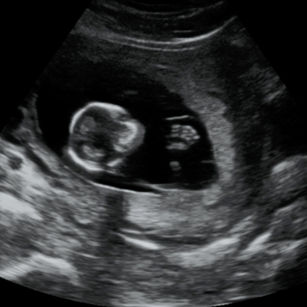

13 Weeks Pregnant

Size: ~2.9 inches (7.4 cm), the size of a Peapod!

Development Highlights:

Baby’s neck lengthens; head more erect.

Bones begin to harden.

Hair follicles forming.

Baby can move arms, legs, and even make tiny sucking motions.